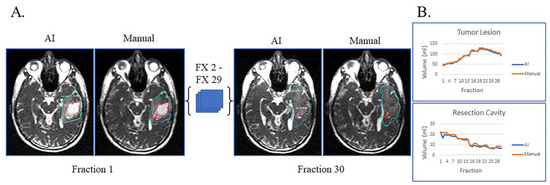

Figure 1A shows an example of a patient with resection cavity only. This case is simple, as the patient had a gross total resection of their disease with no visible tumor lesion left on their MRI-linac bSSFP scans. This patient had subtle resection cavity shrinkage during treatment, picked up by both the deep learning artificial intelligence (AI) and manual segmentations (Figure 1B), and the AI volumes over the 30 treatment fractions track closely with the manually segmented volumes.

Figure 1.

Gross total resection with shrinking resection cavity and no evidence of disease progression on post-treatment MRI. (A) Auto-segmented contours of resection cavity (red) at the first and last treatment fractions (FX) shown on MRI-linac bSSFP. (B) Volumes derived from AI (blue) and manual segmentation (orange) across treatment fractions.